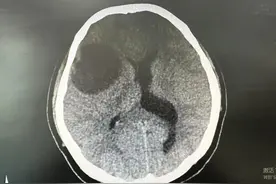

封面新闻记者 喻言“两天用了3.6万元,手术又要花费十来万元,以后还要花多少钱无法估计……”2月7日下午,在重庆医科大学附属第一医院(简称:重医附一院)重症监护室外,张先生焦急地等待着刚刚完成脑部手术的女儿婷婷(化名)。